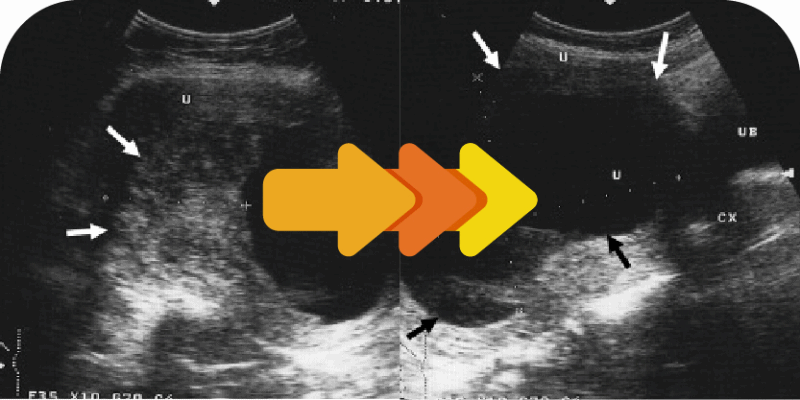

SEBELUM

SELEPAS

“…Syukur cyst dari 5.4cm dah mengecut ke saiz 3cm…Dah nampak perubahan selepas amal rawatan kapsul kunyit ini…”